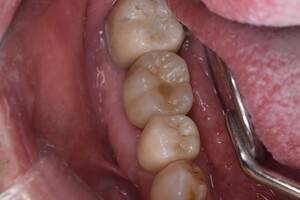

口腔内写真

- Befor

- After

| 年齢 | 50代・男性 |

| 主訴 | 部位:左下6番7番 主訴:左下奥歯腫れて痛い。 |

| 治療内容 | 左下6番抜歯、左下6番7番骨造成、インプラント埋入 |

| 治療費 | 合計:1,232,000円 ・内訳 診断料:55,000円 サージカルガイド2本:66,000円 GBR:110,000円×2本 埋入料:165,000円×2本 静脈内鎮静麻酔:77,000円 2次OPE:22,000円×2本 仮歯:55,000円×2本 上部構造(フルジルコニア):165,000円×2本 (2023年1月現在) |

| 治療期間 | 約8ヶ月 |

| 治療方針 | 元々支台歯に負荷がかかりやすいとされている延長ブリッジを抜歯し、1本単体でしっかりかめるようにインプラントを2本埋入した。骨吸収も進んでいたため、※GBR法で骨造成を同時に行った。 治療と並行して、全顎的な歯周病治療も行い、今後は歯周病が進行しないよう、こまめにメンテナンスに通っていただく。 |

| 担当者所見 | 6番は歯根分割された被せ物が7番の欠損部との延長ブリッジとされており、強い咬合と歯周病も相まって負荷がかかり動揺し、歯として機能しなくなったため、抜歯となった。 |